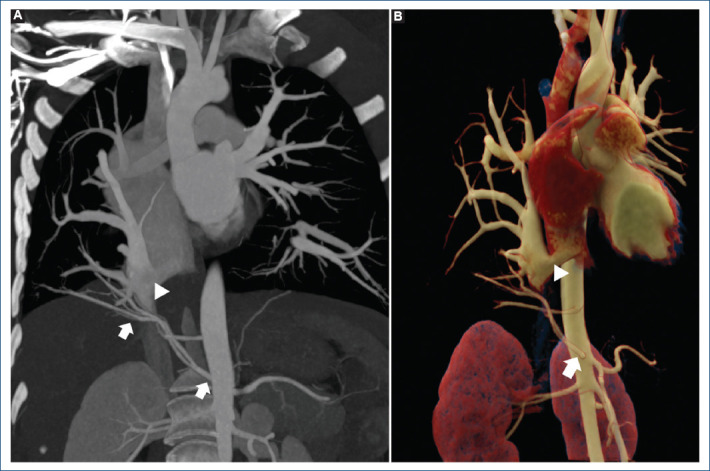

The Ottoman empire sword: a variant of partial anomalous pulmonary veins connections.

{"title":"The Ottoman empire sword: a variant of partial anomalous pulmonary veins connections.","authors":"Karla A Pupiales-Dávila, Vincenzo Arenas-Fabbri, Edgar García-Cruz, Pamela Ramirez-Rangel","doi":"10.24875/ACM.24000029","DOIUrl":null,"url":null,"abstract":"","PeriodicalId":93885,"journal":{"name":"Archivos de cardiologia de Mexico","volume":" ","pages":"122-125"},"PeriodicalIF":0.0000,"publicationDate":"2024-07-29","publicationTypes":"Journal Article","fieldsOfStudy":null,"isOpenAccess":false,"openAccessPdf":"https://www.ncbi.nlm.nih.gov/pmc/articles/PMC12148509/pdf/","citationCount":"0","resultStr":null,"platform":"Semanticscholar","paperid":null,"PeriodicalName":"Archivos de cardiologia de Mexico","FirstCategoryId":"1085","ListUrlMain":"https://doi.org/10.24875/ACM.24000029","RegionNum":0,"RegionCategory":null,"ArticlePicture":[],"TitleCN":null,"AbstractTextCN":null,"PMCID":null,"EPubDate":"","PubModel":"","JCR":"","JCRName":"","Score":null,"Total":0}